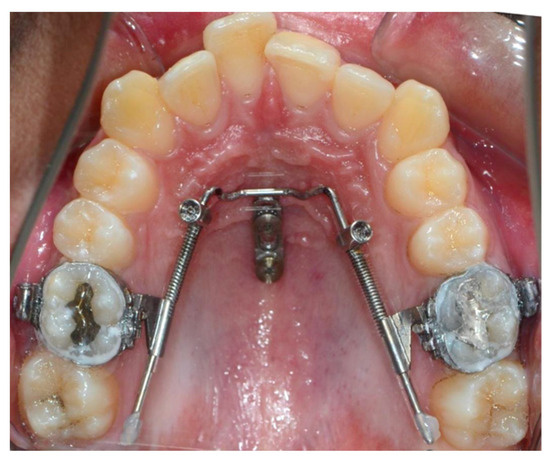

Mini-vis TAD pour béances antérieures avec broches

Béances antérieures

Les dents antérieures ne se touchent pas à la fermeture. L'approche traditionnelle nécessite souvent la chirurgie. Les TADs permettent l'intrusion des molaires pour fermer la béance sans chirurgie.